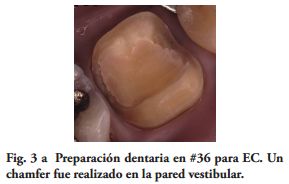

Por su parte, varios estudios clínicos, concluyeron que el remanente coronario es el factor más importante en el éxito clínico del DET (18-21). Por lo tanto, un criterio conservador es esencial en la preparación dentaria para un EC. Toda la superficie oclusal debe ser cubierta por la restauración, teniendo en cuenta la función oclusal del paciente. Los onlays transmiten fundamentalmente, fuerzas compresivas en la interfase adhesiva restauración - diente, mejorando el comportamiento biomecánico (22-24). Para este procedimiento restaurador fue sugerido un espesor oclusal de 3 mm. (25) y aumentando el mismo la resistencia a la fractura sería más alta (26). Además. si las paredes vestibular y/o palatina o lingual, tienen un espesor mayor de 2.0 mm., un chamfer de 1.2 mm. en oclusal de estas paredes, podrían tener un efecto zuncho o abrazadera, aumentando la resistencia a la fractura de los dientes y la retención de la restauración (Figs. 3a, 4a).

Las paredes internas de la corona dentaria y de la cámara pulpar, deben tener una divergencia hacia oclusal mayor de 60 y si presentan depresiones o zonas retentivas, deben rellenarse con cemento de ionómero de vidrio. El operador, dispensa una fina capa del mismo cemento en el piso cameral. En este estudio cuatro preparaciones tenían 3 paredes coronarias (Figs. 1b, 2a), cuatro 2 paredes (Fig. 3a) y en 2, las restauraciones abarcaban 4 paredes coronarias.